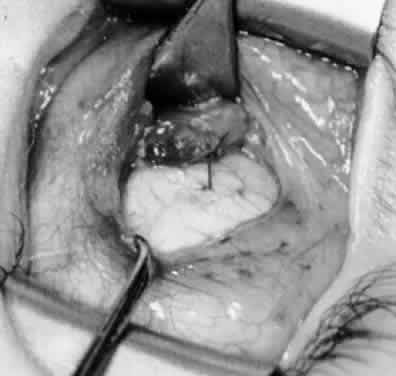

Fig. 28. The inferior oblique muscle is drawn further into the operative field, and a 3-0 Vicryl suture ligature is applied about the belly of the muscle.

Fig. 29. Cautery is used to sever the inferior oblique muscle and to provide hemostasis.

Fig. 30. The stump of muscle is placed through the Tenon's capsule opening. The surgeon must apply sufficient cautery to prevent postoperative bleeding.